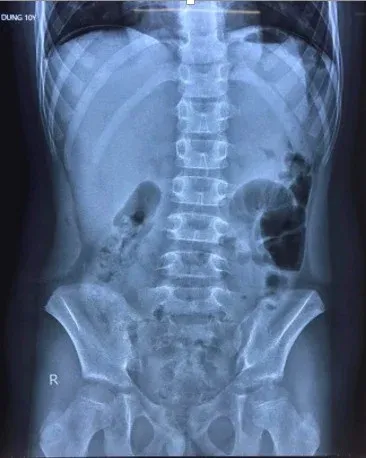

Hình ảnh chụp X-quang cho thấy bệnh nhi có liềm hơi dưới vòm hoành 2 bên, bác sĩ nghi thủng tạng rỗng. Ảnh: Bệnh viện Trẻ em Hải Phòng cung cấp.

Theo hình ảnh chụp X-quang, bệnh nhi có liềm hơi dưới vòm hoành 2 bên. Tại Bệnh viện Trẻ em, bé được chẩn đoán bị viêm phúc mạc do thủng dạ dày/mắc Covid-19.